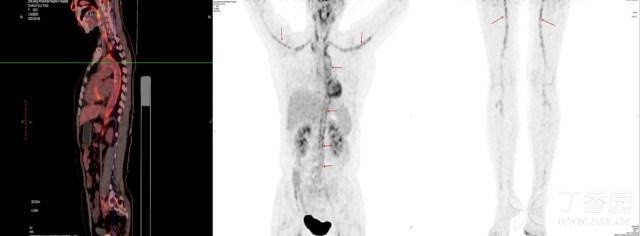

综合上述症状 , 结合发病年龄 , 考虑「颞动脉炎」不能排除 , 遂予完善 PET/CT , 结果回报:多发血管(双侧颈动脉、双侧锁骨下动脉、升主动脉、主动脉弓、胸主动脉、腹主动脉、双侧股动脉)管壁对称性 FDG 代谢增高 , SUVmax 约为 4.6 , 考虑动脉炎(图 1) 。

患者「多发性大动脉炎」诊断基本明确 , 转风湿免疫科予甲泼尼龙针 40 mg qd 治疗 , 患者头痛缓解 , 体温逐步恢复正常(图 2) 。